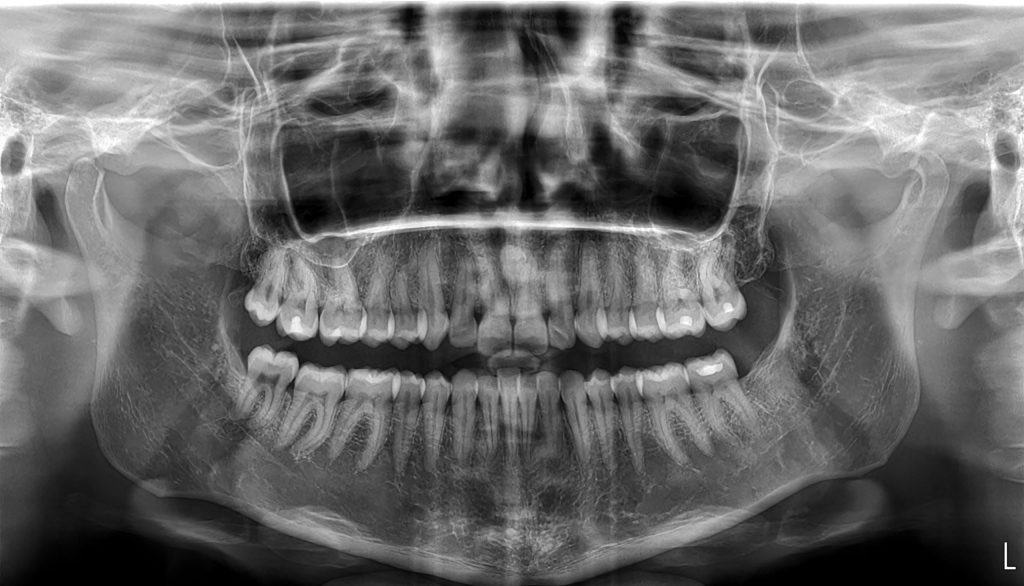

1. ΠΑΝΟΡΑΜΙΚΗ ΑΚΤΙΝΟΓΡΑΦΙΑ

Η πανοραμική ακτινογραφία (Ορθοπαντομογράφημα) είναι η συχνότερα χρησιμοποιούμενη οδοντιατρική ακτινογραφία για τη μελέτη των δοντιών και των γνάθων. Το βασικό της πλεονέκτημα είναι ότι επιτρέπει με τη λήψη μιας ακτινογραφίας τη μελέτη όλων των δοντιών του στόματος, των οστών της άνω και κάτω γνάθου, των κροταφογναθικών διαρθρώσεων, καθώς και τμήματος των ιγμορείων άντρων.

Στην οδοντιατρική χρησιμοποιείται για τη μελέτη οδοντικών και περιοδοντικών παθήσεων, οστικών παθολογικών αλλοιώσεων και καταγμάτων. Αποτελεί χρήσιμο διαγνωστικό εργαλείο για τη σύνταξη του σχεδίου θεραπείας από τον οδοντίατρο.

Η λήψη της είναι γρήγορη (διαρκεί περίπου 13-16 sec) και ανώδυνη. Τα ψηφιακά συστήματα ακτινογράφησης που έχουν αναπτυχθεί και εξελιχθεί σημαντικά τα τελευταία 15 χρόνια έχουν επιτρέψει επίσης τη σημαντική μείωση της δόσης ακτινοβολίας που δέχεται ο εξεταζόμενος.